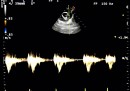

Avantaggiato fotografa animali, padroni, attrezzatura e ambienti all’interno di diversi ambulatori veterinari, con l’idea che «l’eccellenza clinica è al servizio dell’animale e l’animale è più uomo dell’uomo». Attraverso immagini di ambienti sterili, freddi e tecnologici, Avantaggiato sottolinea questa che lui definisce una anomalia: cliniche pulite e all’avanguardia messe al servizio degli animali. Con i suoi ritratti prova a personificare il “paziente”, per sottolineare ancora di più questo aspetto.